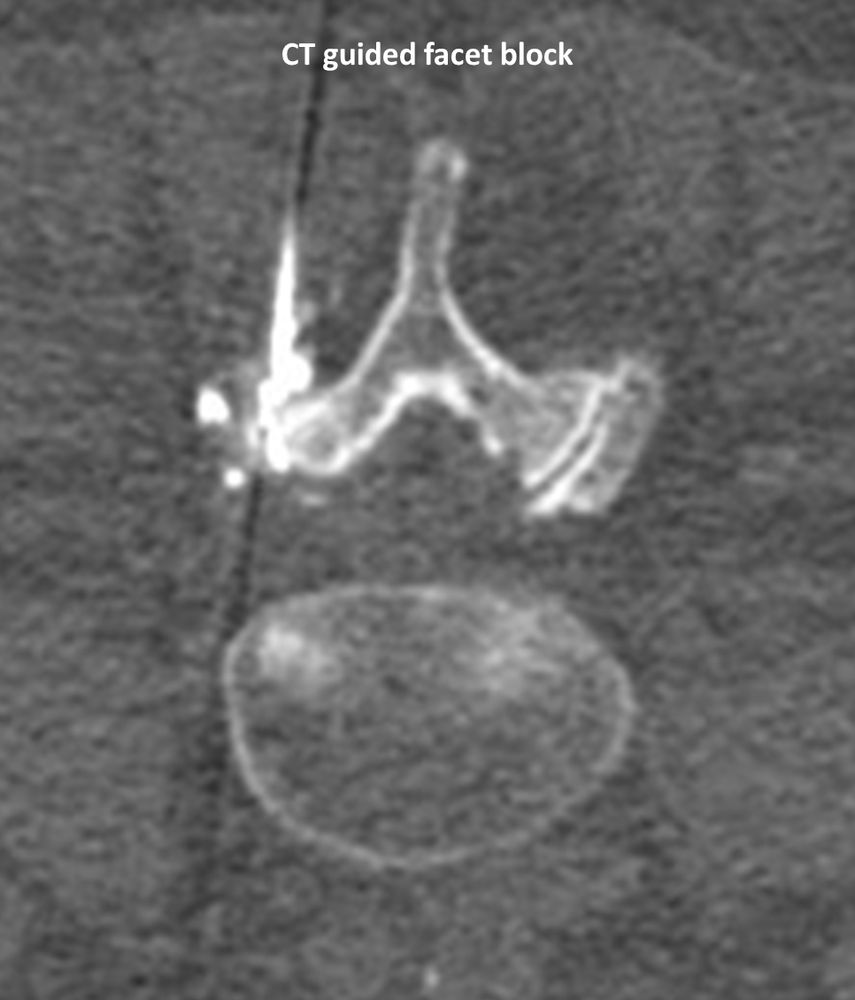

Με την βοήθεια της επεμβατικής ακτινολογίας είναι δυνατόν να πραγματοποιηθούν διαφορες ενέσιμες τεχνικές που αποσκοπούν στη μείωση του μυοσκελετικού πόνου, την ενίσχυση της αποτελεσματικότητας της φυσιοθεραπείας και την επιτάχυνση της διαδικασίας επούλωσης. Οι τεχνικές αυτές περιλαμβάνουν την κατευθυνόμενη έγχυση φαρμάκων ή πραγματοποίηση θεραπευτικών χειρισμών ακριβώς στη θέση τηςπαθολογία. Ετσι εξασφαλιζεται η μέγιστη αποτελεσματικότητα ( έως 95% κατά περίπτωση) και ασφάλεια σε σχέση με τυφλούς χειρισμούς χωρίς ακτινολογική καθοδήγηση.